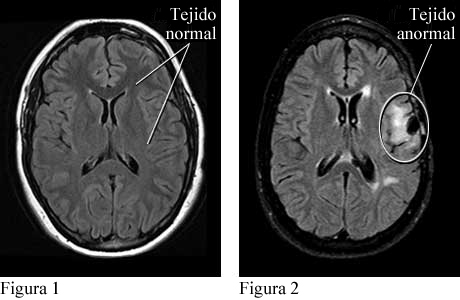

Imágenes de tejido cerebral normal y tejido cerebral anormal que causa convulsiones

Cortesía de Intermountain Medical Imaging, Boise, Idaho. Todos los derechos reservados.

Las vistas de arriba del cerebro muestran tejido normal (ver figura 1) y tejido anormal (provocado por una lesión) que causa convulsiones (ver figura 2).